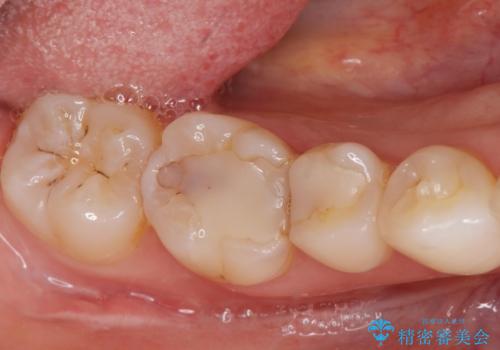

歯茎が腫れた。ジルコニアクラウンやりかえ。

- メンテナンスで来院された患者様です。

歯茎が腫れたとの事で歯の神経が失活していたので精密根管治療を行い、ジルコニアクラウンで治療を行いました。

神経が失活しているので痛みは感じにくいですがこのまま放置をしてしまうと骨が溶けたり痛みが出たりします。

このように歯茎にニキビみたいな物が出た場合、あるいは存在する場合すぐに歯科医院に相談することをおすすめします。